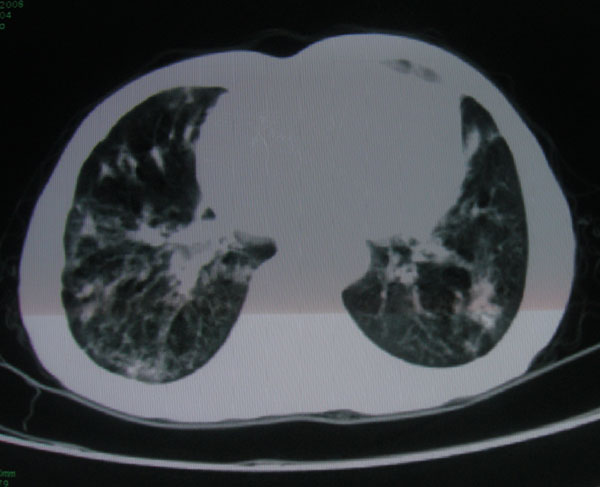

标题: CT15046:F59Y,咳嗽间断咳血丝痰就诊. [打印本页]

标题: CT15046:F59Y,咳嗽间断咳血丝痰就诊.

咳嗽\间断咳血丝痰就诊.

本例应该是“慢性疾病并发多种合并症”即:慢支并感染并支气管扩张征!结合病灶分布 形态分析,不除外合并“继发性肺结核”!

肺间质性改变 支气管扩张合并感染

慢性支气管炎伴全小型肺气肿、支气管扩张、感染、间质纤维化。

慢性支气管炎伴支气管扩张、感染,间质纤维化。

慢性支气管炎伴全小叶型肺气肿、支气管扩张、感染、间质纤维化